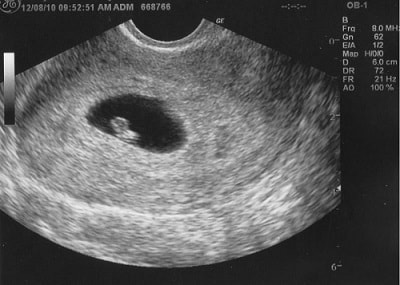

Tuy thai 5 tuần đã nghe được tim thai, nhưng khi nhìn vào hình ảnh siêu âm thai nhi 5 tuần tuổi, mẹ chưa thấy rõ được các đường nét trên khuôn mặt bé. Lúc này, bé vẫn chỉ ở dạng phôi thai hình chữ C cong nhẹ, chưa được gọi là thai nhi và cũng chưa “ra dáng” một em bé hoàn chỉnh.

Khi thực hiện siêu âm ở giai đoạn này, mẹ sẽ được nhìn thấy một số đặc điểm rõ nét hơn 4 tuần trước đó. Cụ thể: